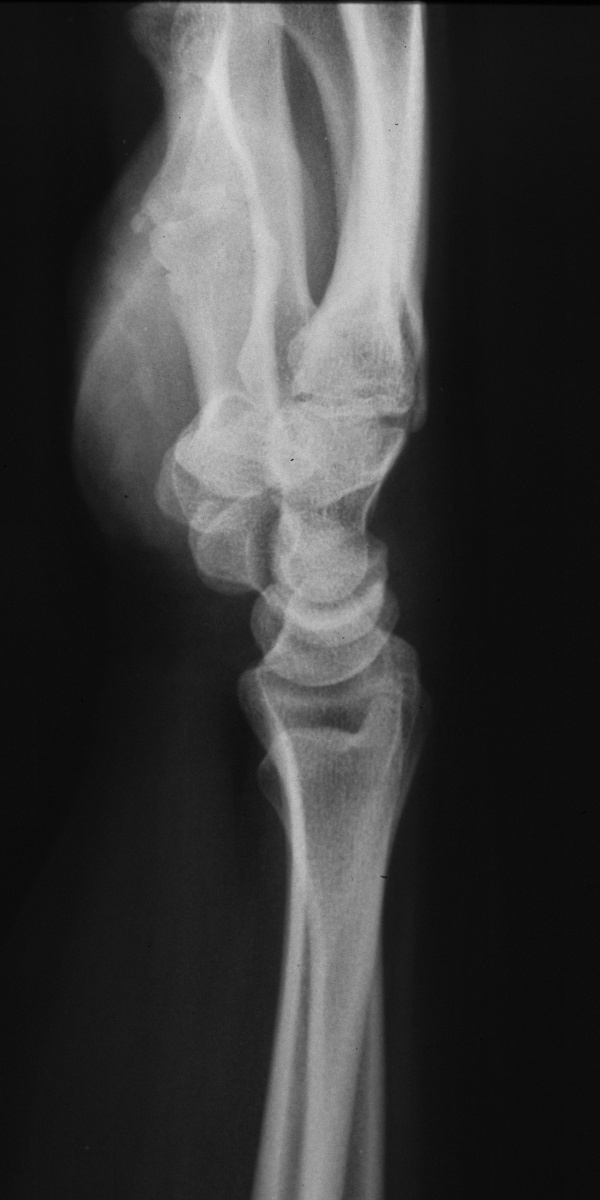

| Opposite side, asymptomatic: |